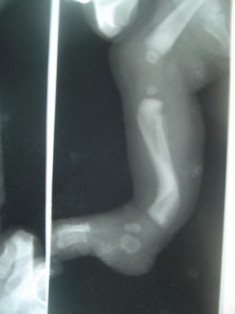

Postero-Medial Bowing of Tibia is a congenital condition characterized by a curvature or bending of the tibia bone, which is one of the two bones in the lower leg. This condition usually becomes apparent during infancy or early childhood. While the

exact cause of this condition is not always known, it is believed to be related to factors affecting fetal bone development.

The most noticeable symptom of Postero-Medial Bowing of Tibia is the

inward curving of the tibia bone, which may lead to a bowlegged appearance. Other symptoms can include uneven leg lengths, difficulty walking or standing, and potential discomfort as the child grows. Diagnosis typically involves a thorough physical examination, medical history review, and often imaging studies such as X-rays.